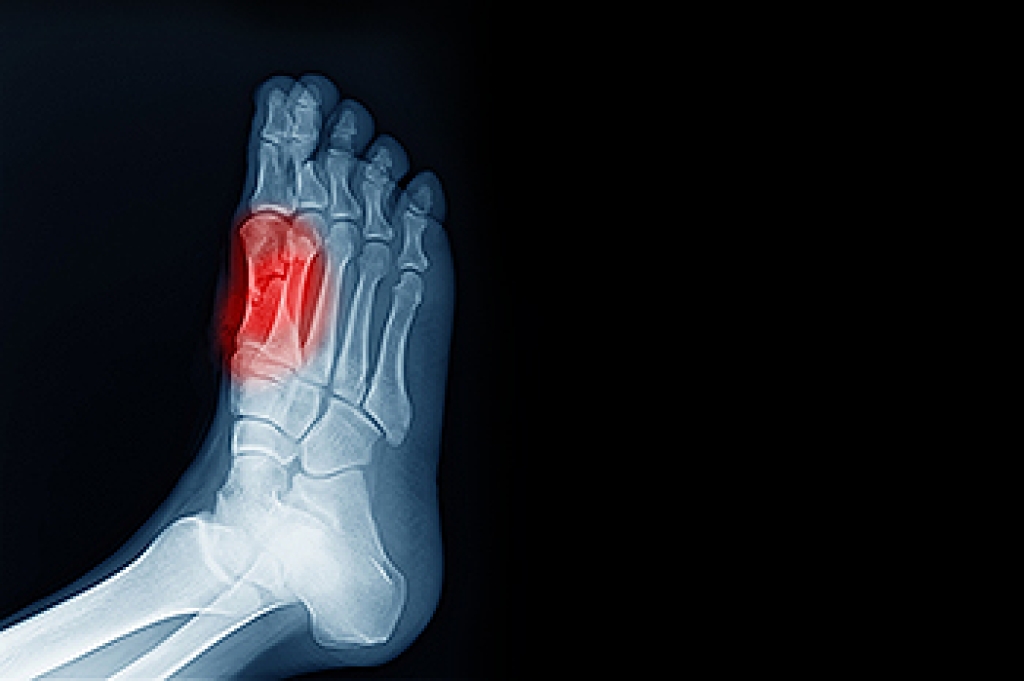

Standing on your feet for long periods of time can cause stress and pain in your feet. Your whole body may experience change in terms of posture, back pain, bunions, callouses and or plantar warts. There are ways to avoid these conditions with proper foot care, smart choices and correct posture.

If you have any questions please contact our office located in Lanham, MD . We offer the newest diagnostic and treatment technologies for all your foot and ankle needs.